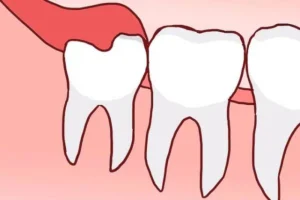

2.1 Swelling Around the Gums

One of the first and most noticeable signs of wisdom tooth eruption is gum swelling. As the tooth begins to push through, the gum tissue at the back of your mouth may appear puffy, tender, or reddened. This can create a sensation of pressure or discomfort, especially when eating or brushing your teeth.

3.4 Gum Flap (Pericoronitis) Around Wisdom Teeth

A partially erupted tooth may have gum tissue covering it, which can become infected or swollen. This area easily traps food and bacteria, causing persistent pain and unpleasant odor. Gum flaps are especially common with lower wisdom teeth and often require surgical removal or other treatments.